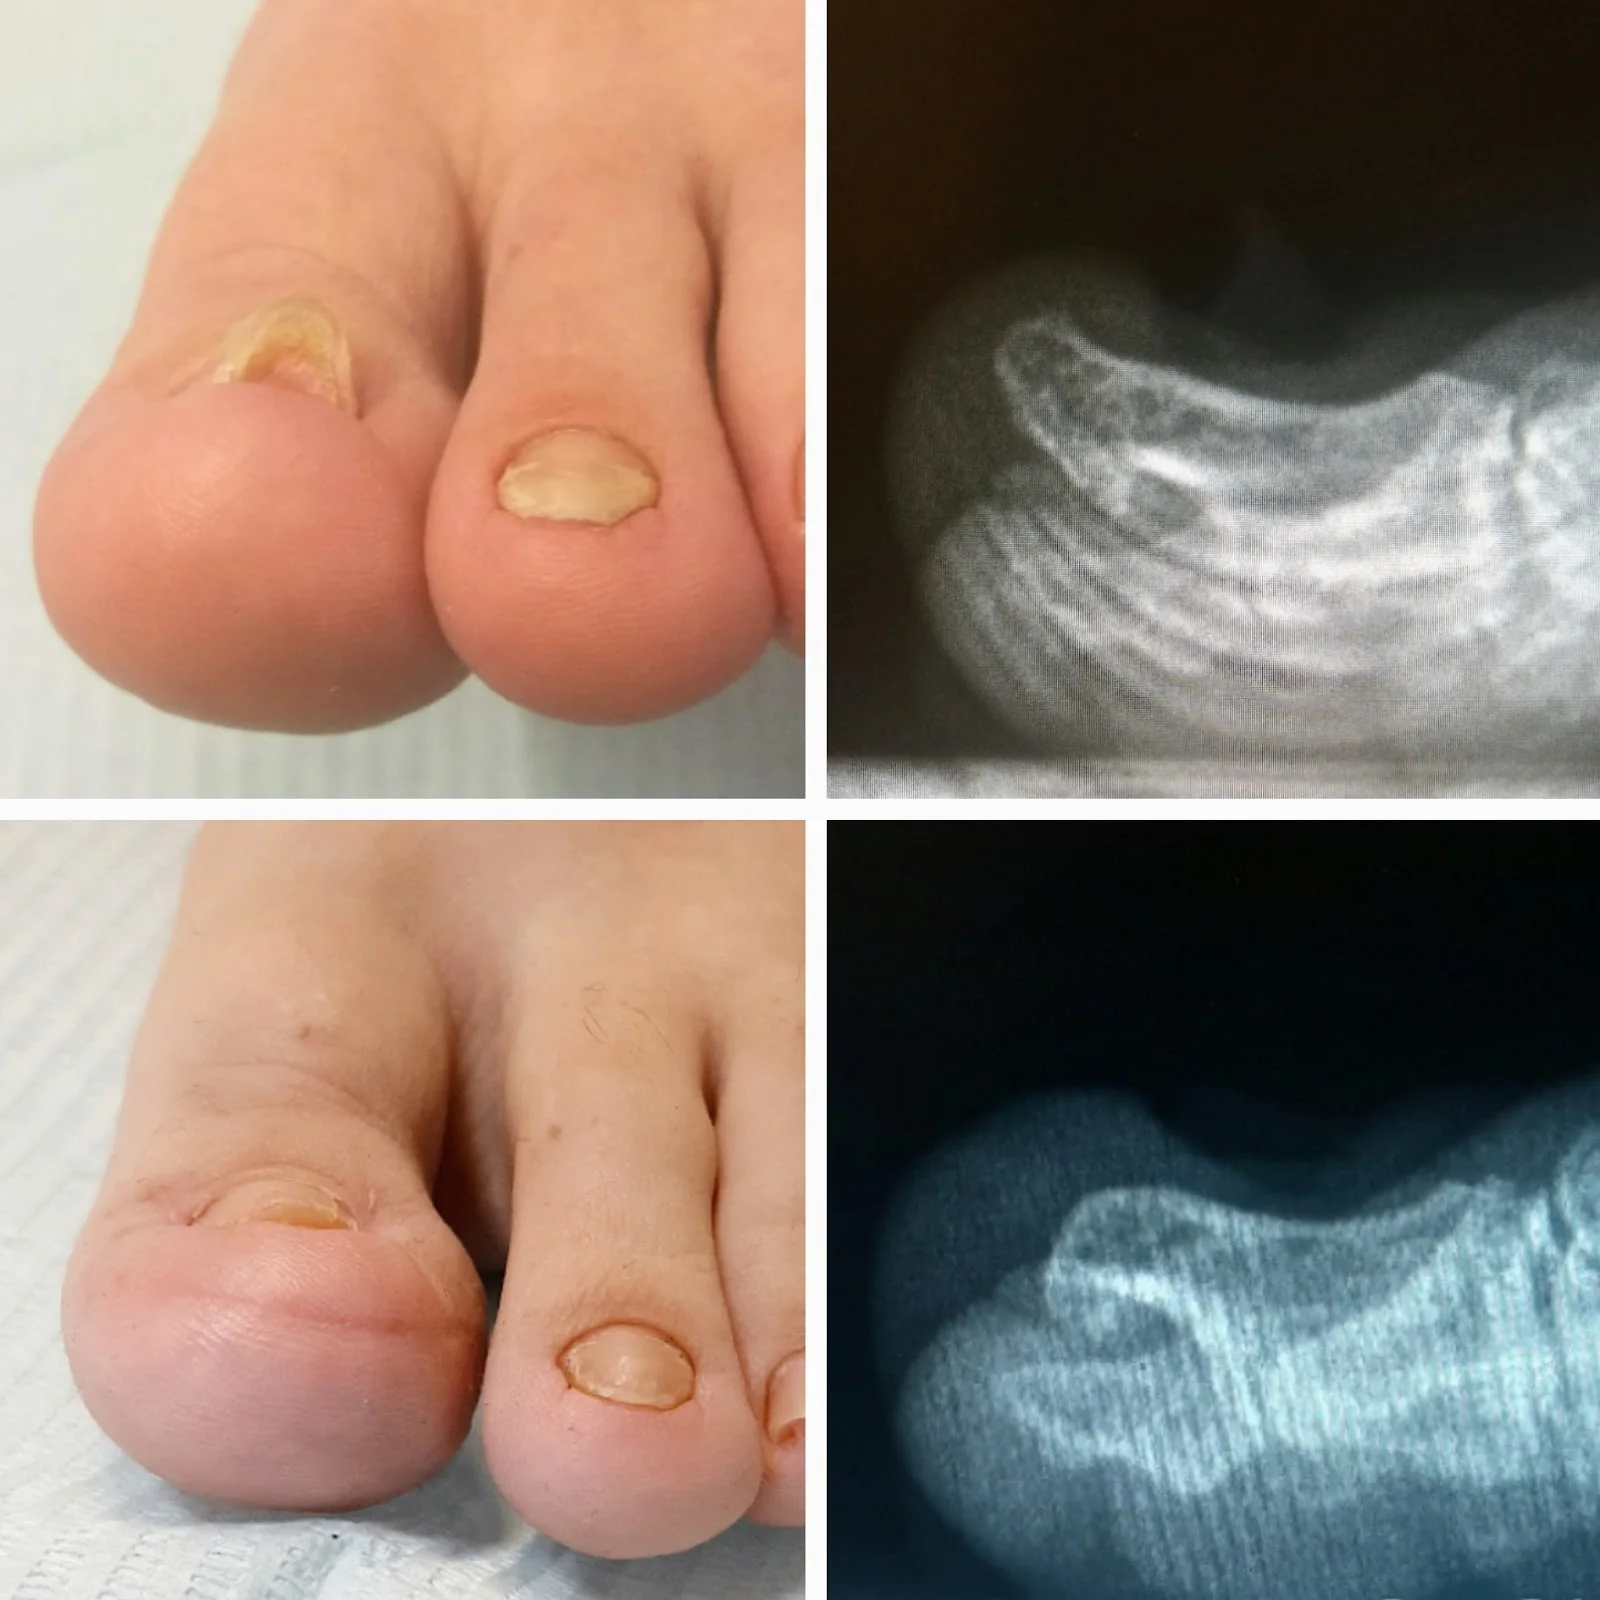

Galería de Kinderarzt Dirk Müller-Liebenau